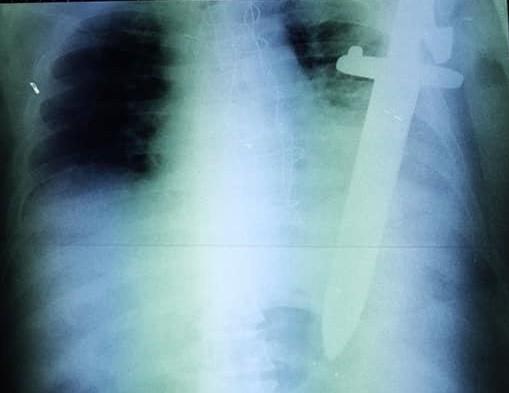

Ảnh chụp X-Quang cây dao cắm trong ngực bệnh nhân. |

Ngày 27/8/2018, nguồn tin từ Bệnh viện Đa khoa TP Cần Thơ cho biết, các bác sĩ của ngoại Lồng ngực Mạch máu của bệnh viện này vừa phẫu thuật thành công, cứu bệnh nhân tự đâm xuyên thấu ngực trái.

Theo người nhà, trong phút yếu lòng, bệnh nhân đã dùng dao tự đâm vào tim để kết liễu mạng sống.

Kết quả thăm khám cho thấy: bệnh nhân tổn thương từ khoảng liên sườn 3, đường trung đòn bên trái xuyên thủng vào màng tim, thủng cơ hoành, đứt động mạch gây tràn máu màng phổi. Sau khi hội chẩn, bệnh nhân được chỉ định phẫu thuật khẩn cấp.

Bệnh nhân được tiến hành gây mê nội khí quản kiểm soát đường thở. Tiến hành mở ngực phía dưới cây dao và rút dao ra ngoài. Vị trí vết thương thấu ngực đứt bó mạch liên sườn nên các bác sĩ phải khâu cầm máu động mạch. Sau đó, các bác sĩ tiến hành kiểm tra khoang màng tim, màng phổi trái, lượng máu lấy ra được khoảng 700ml. Cuối cùng, các bác sĩ đặt dẫn lưu, khâu vết thương. Trong suốt quá trình phẫu thuật, bệnh nhân phải truyền 2 đơn vị máu. Ca mổ hoàn thành sau hơn 1 giờ.

Theo các bác sĩ, đây là một trường hợp tai nạn thương tích nặng cần xử trí nhanh và chính xác nhằm tránh nguy cơ đáng tiếc có thể xảy ra. Ngoài tiền sử bị thiếu máu cục bộ cơ tim và bệnh nhân còn bị tiểu đường type 2. Bệnh nhân đã phẫu thuật tim bắt cầu mạch vành và đang sử dụng thuốc kháng đông máu. Điều này khiến cho việc cầm máu trong lúc mổ khó khăn và vết thương sau mổ lâu hồi phục.